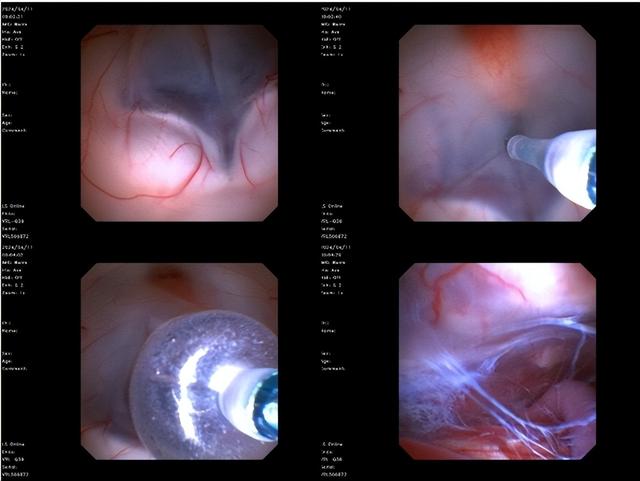

肖庆主任团队为患者实施“神经内镜下第三脑室底造瘘术”,通过仅1厘米的颅骨锁孔,运用超细软性内镜精准抵达深部脑室:

1. 创新性采用双腔球囊导管系统,在垂体漏斗与乳头体间安全造瘘并扩张至4mm

2. 同期松解基底池粘连、穿通Liliequist膜,实现脑室-基底池全程沟通